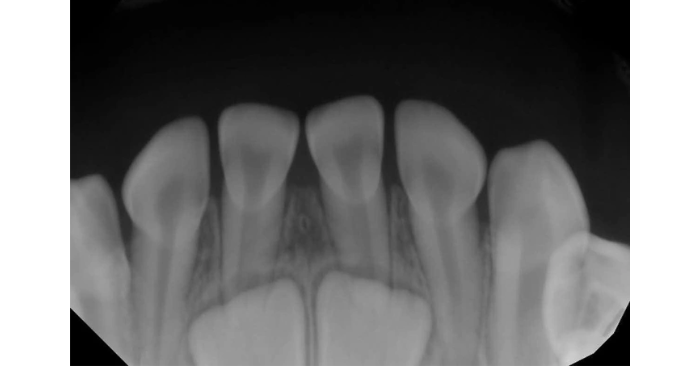

Răng vĩnh viễn mọc từ khoảng 5 đến 12 tuổi. Khi trẻ lớn, xương hàm mở rộng; khuôn mặt thay đổi và cần số răng lớn hơn để đáp ứng nhu cầu nhai. Chính vì vậy, răng vĩnh viễn có kích thước lớn hơn và số lượng nhiều hơn răng sữa.

Bộ răng này gồm 28 chiếc, có thể thêm bốn răng khôn tùy cơ địa. Nhờ sự phân chia chức năng – răng cửa cắn; răng hàm nghiền – con người có thể thưởng thức chế độ ăn đa dạng. Đây là đặc điểm riêng biệt của loài người; phản ánh sự thiết kế tinh tế, không liên quan đến giả thuyết tiến hóa từ động vật.